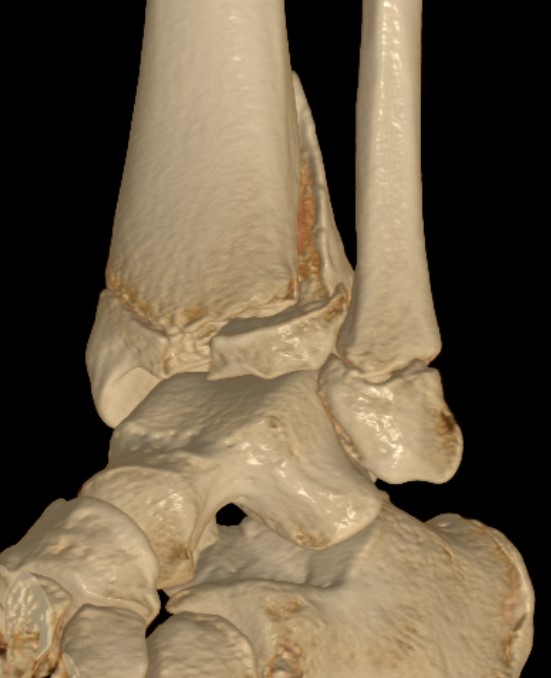

Triplanar Fracture

Definition

Fracture in coronal, sagittal and transverse planes

- crosses epiphysis

- passes through growth plate

- extends into metaphysis

Xray

AP xray: Salter-Harris type III / Tillaux

Lateral xray: Salter-Harris Type II

CT

Coronal images: Salter-Harris type III

Sagittal images: Salter-Harris type II

Axial images: 3 point star